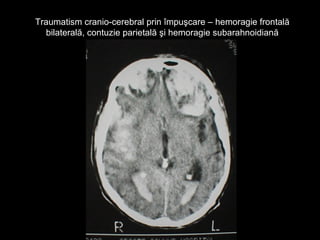

Traumatism cranio-cerebral prin împuşcare – hemoragie frontalăTraumatism cranio-cerebral prin împuşcare – hemoragie frontală

bilaterală, contuzie parietală şi hemoragie subarahnoidianăbilaterală, contuzie parietală şi hemoragie subarahnoidiană